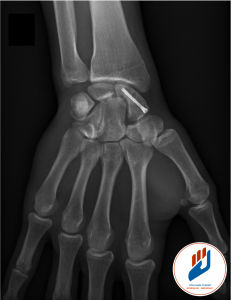

En revanche, si la fracture est déplacée, instable ou si elle tarde à consolider, une intervention chirurgicale est nécessaire. Cette chirurgie consiste à fixer l’os avec une vis (le plus souvent sous contrôle arthroscopique et, si besoin, d’y associé à une greffe osseuse.

Le traitement chirurgical de la fracture du scaphoïde se déroule sous anesthésie locorégionale, ce qui permet d’endormir uniquement le bras. Le plus souvent le traitement se fait par une courte incision. Si une arthroscopie est associée, deux petites incisions sont réalisées sur le dos du poignet pour introduire une caméra miniature et des instruments spécifiques.

La fracture est soigneusement reduite sous contrôle visuel direct. Si besoin, un greffon osseux spongieux est ensuite prélevé au niveau du radius distal, à proximité immédiate du site opératoire et positionné dans le foyer de fracture. La fracture est ensuite stabilisée à l’aide d’une vis ou de broches, selon le cas.

L’intervention est rapide, précise, et réalisée en chirurgie ambulatoire. Le patient peut rentrer chez lui le jour même, avec une immobilisation adaptée.